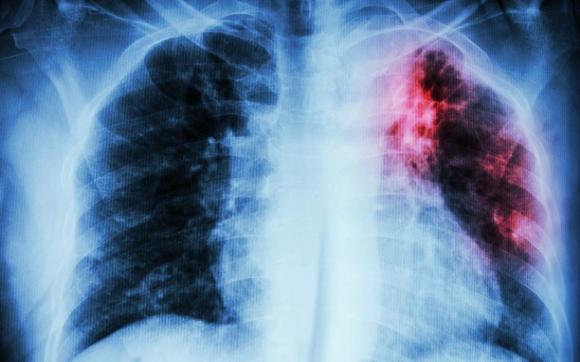

Алтайский край - в числе лидеров среди регионов по заболеванию туберкулезом

По словам гл. фтизиатра края Елены Анисимовой, все люди являются инфицированными, просто когда иммунитет слабеет, тогда заболевание начинает прогрессировать. Первые признаки заболевания – общая интоксикация организма. Однако человек не распознает начало туберкулеза, поэтому важно проходить флюорографию.

Туберкулез поражает практически весь организм, кроме ногтей и волос. При этом непросто подобрать лечение для пациентов.